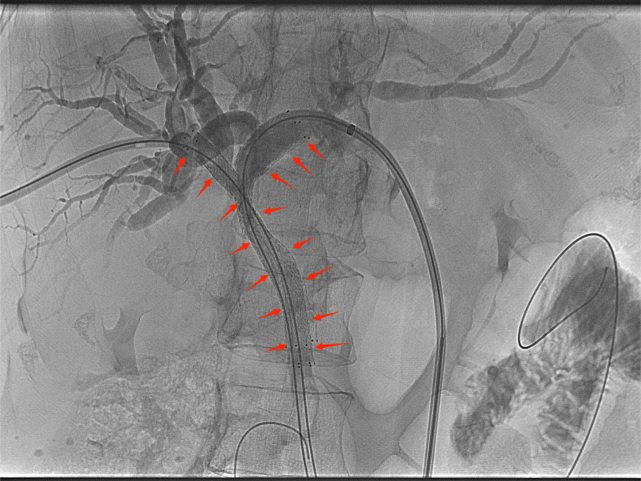

![]() 【经皮胆道支架置入术】 ![]() 胆道支架置入能很好地弥补经皮肝穿刺胆道引流术的不足之处,通过在胆管狭窄/阻塞处安置金属支架,解除胆道梗阻、恢复通畅,促进胆汁入肠,改善消化功能的同时无需长期带管,显著提高了生活质量,适合短期内有效解除胆道梗阻的患者(如恶性胆道梗阻)。 ![]() 低位胆道梗阻支架置入 ![]() 高位胆道梗阻支架置入 变身“小金人”并不可怕,找准病因,用对方法,也能轻松退黄。介入治疗应用于胆道梗阻多年,技术成熟,安全且高效。市四医院介入室能常规开展各类复杂胆道梗阻的介入治疗,高效扫“黄”,为肝功能保驾护航。